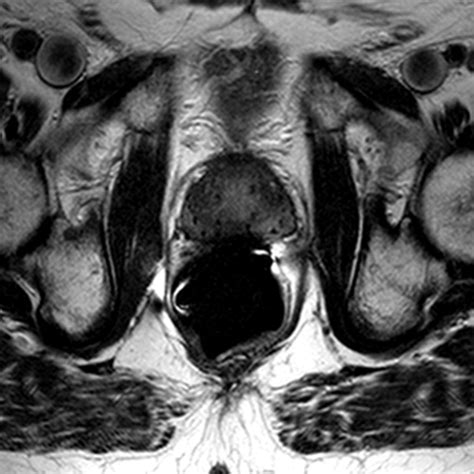

• Multiparametric MRI (mpMRI): This technique combines multiple MRI sequences, including T2-weighted imaging, diffusion-weighted imaging (DWI), and dynamic contrast-enhanced (DCE) imaging, to provide a comprehensive evaluation of the prostate.

• Prostate Imaging Reporting and Data System (PI-RADS): This standardized reporting system helps radiologists interpret MRI findings and classify the likelihood of clinically significant prostate cancer.